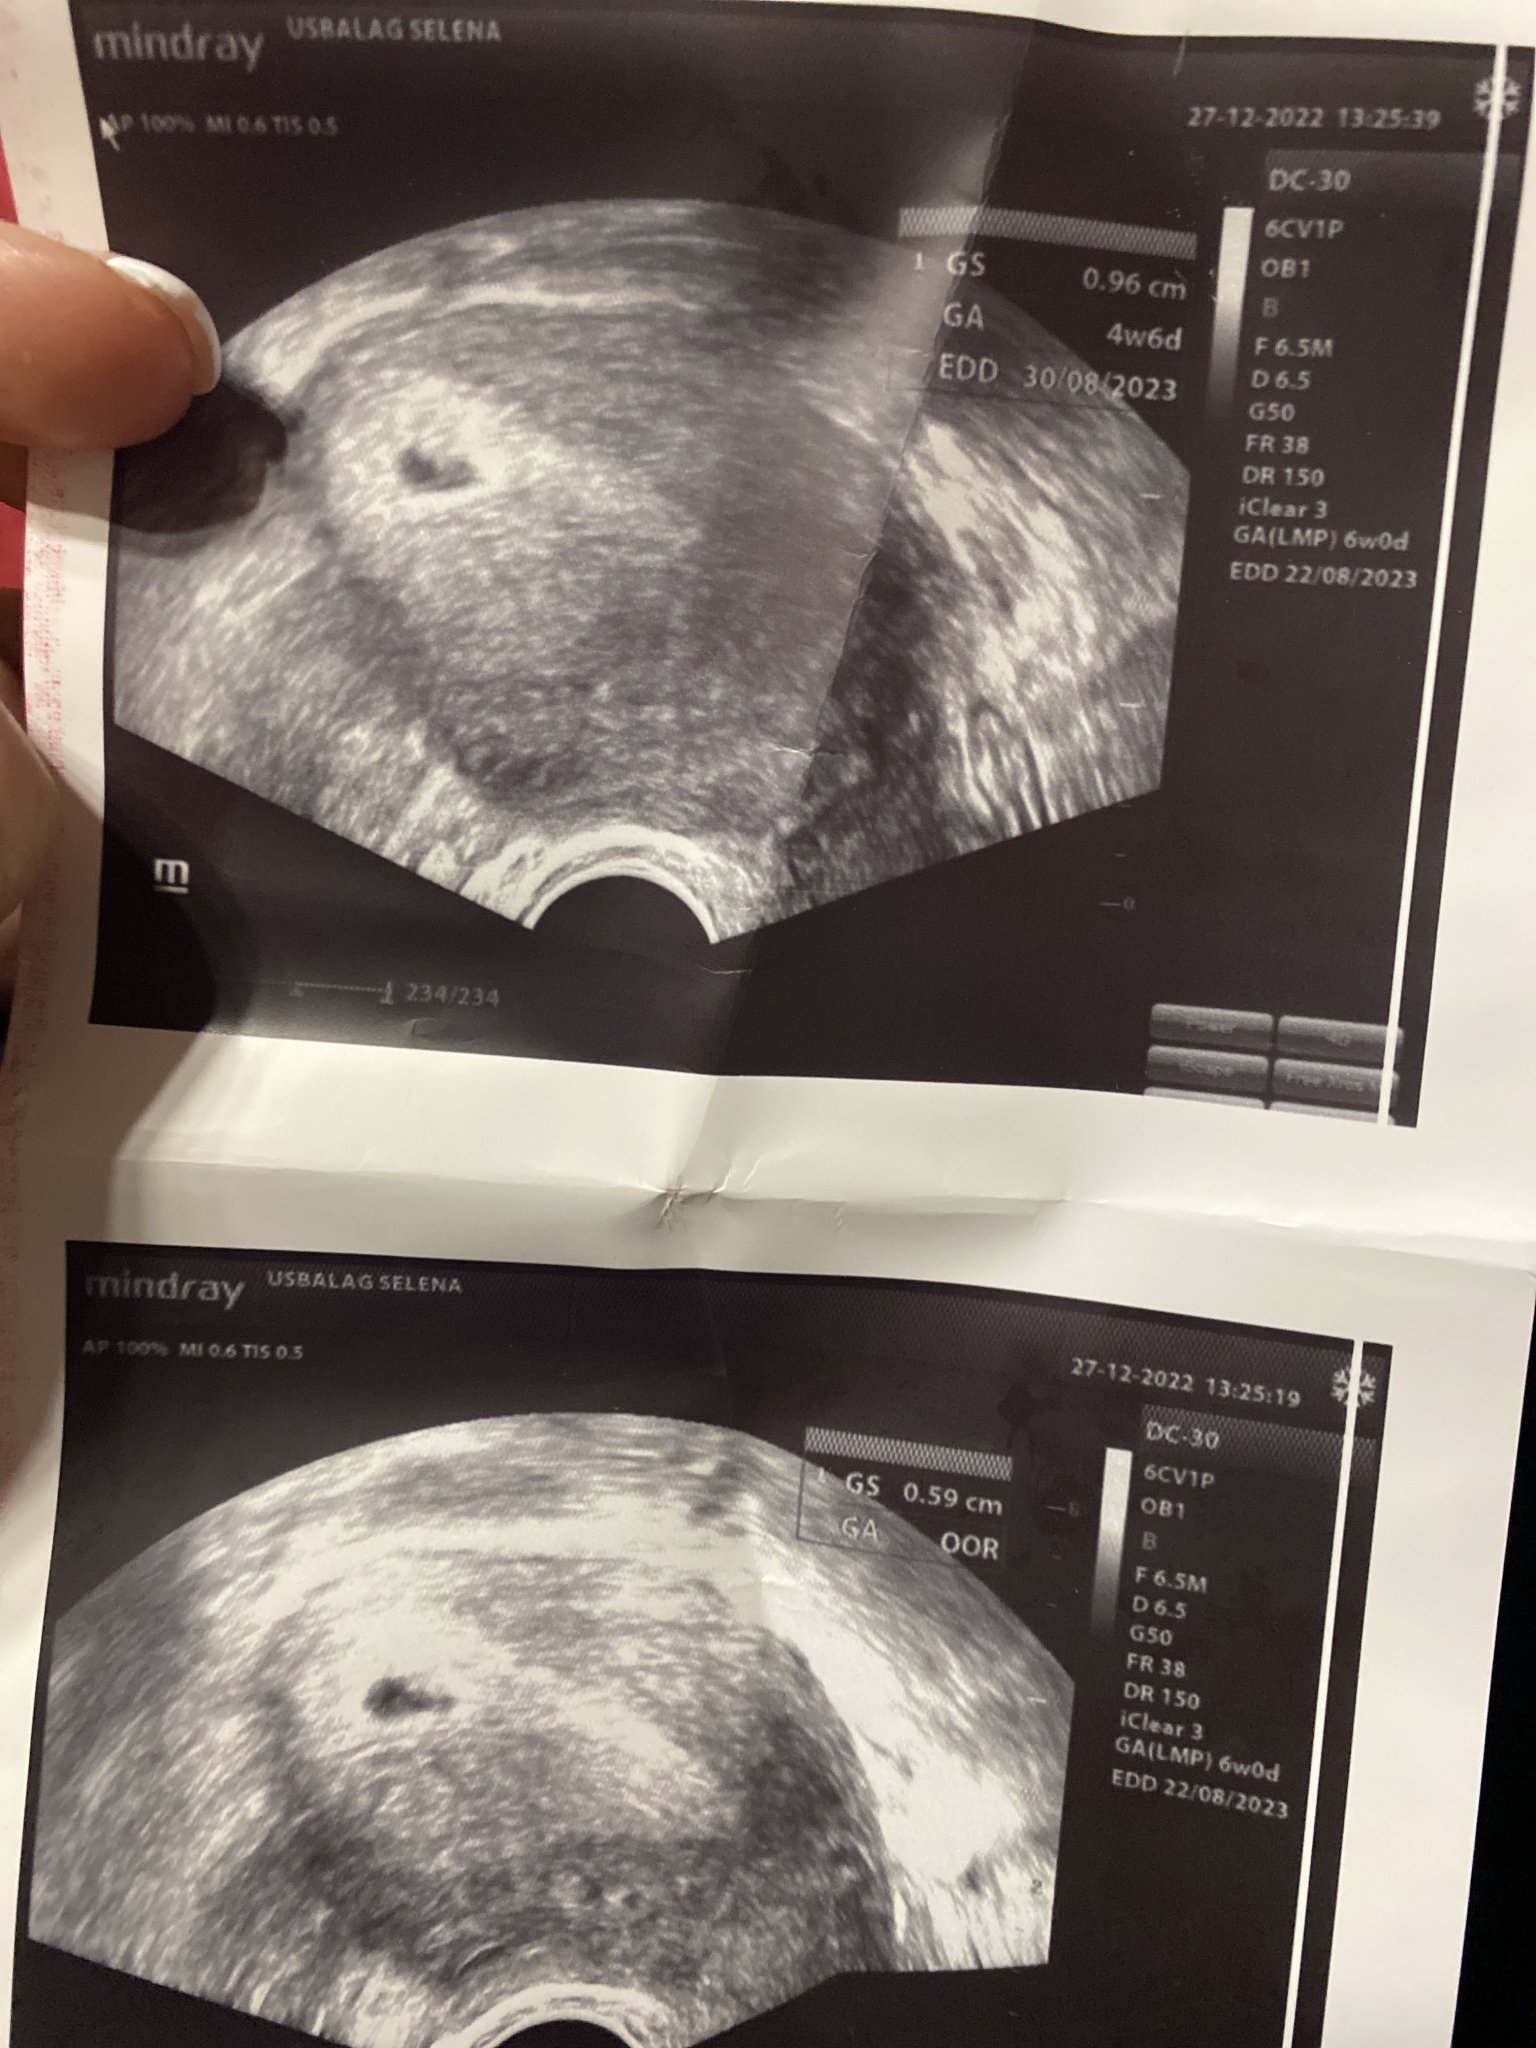

Здравейте! Някой би ли ми казал това нормално изглеждаща бременност ли е,при положение че съм в 5 седмица и 3-4 дни (знам кога ми е била овулацията) На едната снимка пише 9мм плоден сак,другата 6… нямам идея кое е вярно.Вече си мисля че трябваше и жълтъчно мехурче да има.

Вижда се само плоден сак,но на снимката пише че сте в 4г.с и 6дни.Според мен за тези седмици е нормално.

Както моята снимка изглежда.Нормално е всичко,не се притеснявай